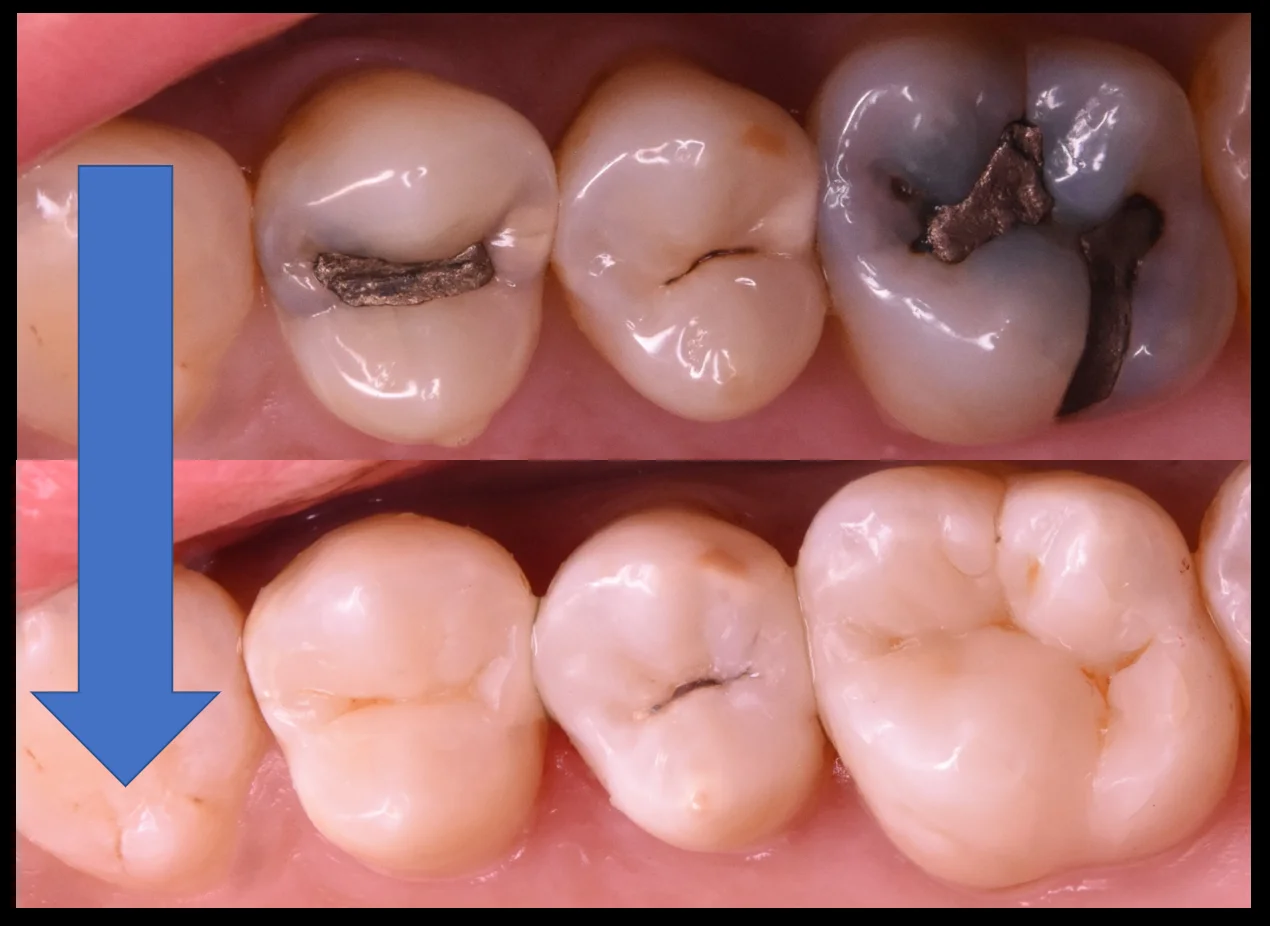

そして治療終了後の写真がこちらです。

いかがでしょうか?

比較的違和感なく詰められたかと思います。

個人的には真ん中の歯の溝の色に合わせてステイン(人工的な着色)を入れられたのがよかったかと思います。

術前術後の比較の写真はこちらになります。

3本を一気に1日で終了完了できるのはダイレクトボンディングの非常に大きなメリットの一つですね。